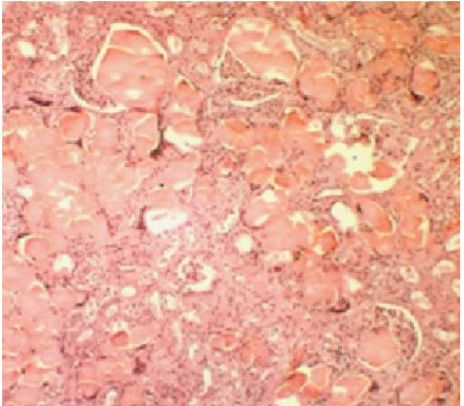

17. 一位54 歲女性,沒有糖尿病或有高血壓,但是有 proteinuria (2.4 g/24 hr), microscopic hematuria, 及polymyalgia。其他實驗室檢查: , Hb 8.6, MCV 90 (fL), MCHC 32 g/dL. serum creatinine 2.2 mg/dL, hypercalcemia ([Ca] 11.8 mg/dL), 及 urinary monoclonal protein。腎臟生檢(renal biopsy,結果如附圖)。病人的診斷最可能是:

(A) Wegener's granulomatosis (B) multiple myeloma (C) Hemolytic Uremic Syndrome (D) systemic lupus erythematosus (SLE) (E) Henoch-Schonlein Purpura